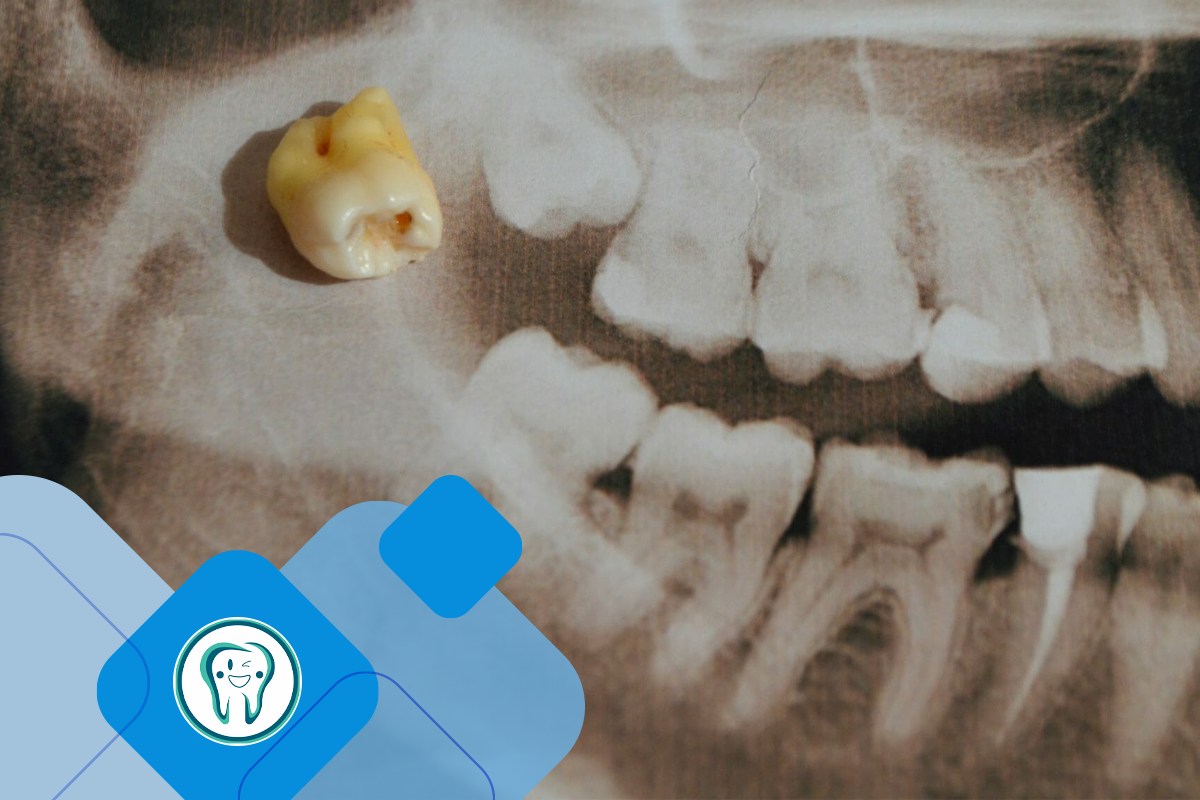

برای مدیریت این علائم، ارزیابی زودهنگام دندانپزشکی و گرفتن عکس رادیوگرافی ضروری است. دندانپزشکان ممکن است نظارت بر دندان، تمیز کردن کامل ناحیه یا برداشتن جراحی را بسته به شدت مشکل پیشنهاد کنند.

فرآیند تشخیص: تشخیص درد دندان عقل به طور کلی شامل معاینه دندانی است که در آن دندانپزشک علائم قابل مشاهده پوسیدگی، نهفتگی یا عفونت را بررسی می کند. ممکن است برای مشاهده موقعیت دندان عقل در داخل فک و تعیین اینکه آیا نهفتگی یا عفونت زیر خط لثه وجود دارد، اشعه ایکس گرفته شود. این به برنامه ریزی استراتژی های درمانی مناسب، مانند استخراج یا دارو کمک می کند.